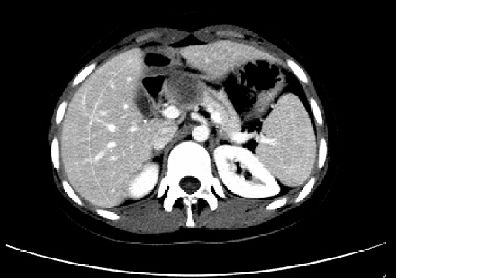

11月28日,胰腺外科李可洲教授完成了我院首例完全腹腔镜胰腺中段切除手术。患者为一名来自于贵州省毕节市的18岁青年女性,患者入院前曾在当地某三甲医院就诊,诊断为胰腺肿瘤,但因医生告知手术风险巨大,要求患者继续观察,故而患者转至我院进一步诊治,我院CT检查提示胰腺实性假乳头状肿瘤可能。李可洲教授充分评估了手术风险,经过全科术前讨论后,拟行腹腔镜手术探查。术中发现胰颈部直径约100px肿瘤,边界尚清楚,活动度尚可。经过历时7小时的全腹腔镜手术治疗,完成了胰腺肿瘤切除,近端胰腺残端封闭,远端胰腺空肠吻合术。术后患者恢复顺利,术后3天排气,进食尚正常,无明显腹痛感,引流管如期拔除,术后7天患者顺利出院。此项手术的成功开展是我院腹腔镜技术的又一进展,为推广腹腔镜技术奠定了基础。